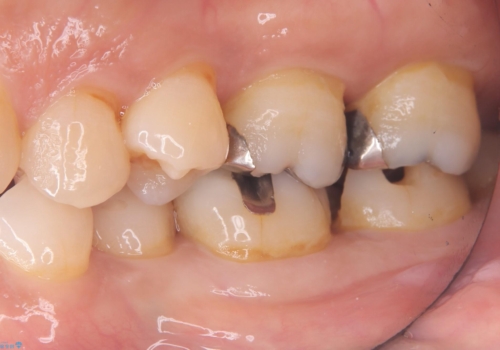

左下7番目の歯の詰め物が外れ、セラミックインレーでのやり替えとなりました。

隣在歯にも保険適用もメタルインレーが入っており、咬合面のインレーと歯質の境目が虫歯になっていたこともあり、合わせてのやり替えとなりました。

左下7番めの歯、フロスを通したらインレーが外れてしまったとのことで、適合具合の精密さや、これを機に白い詰め物にしたいとのことからセラミックインレーでのやり替えとなりました。

また、6番目の歯にも保険適用のメタルインレーが入っており、咬合面インレーと歯質境目にう蝕を認め合わせてのやり替えとなりました。